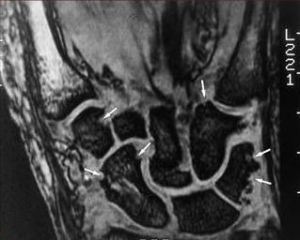

2.受累關節及胸部X線攝片、心電圖檢查。必要時行超聲心動圖檢查。

①每日關節晨僵至少1h(≥6周);②3個或3個以上關節腫(≥6,周);③腕、掌指關節或近端指間關節腫(≥6周);④對稱性關節腫(≥6周);⑤皮下結節;⑥手X線片改變;⑦類風濕因子陽性(滴度>1∶32)。具備4條或4條以上標準,可確診。